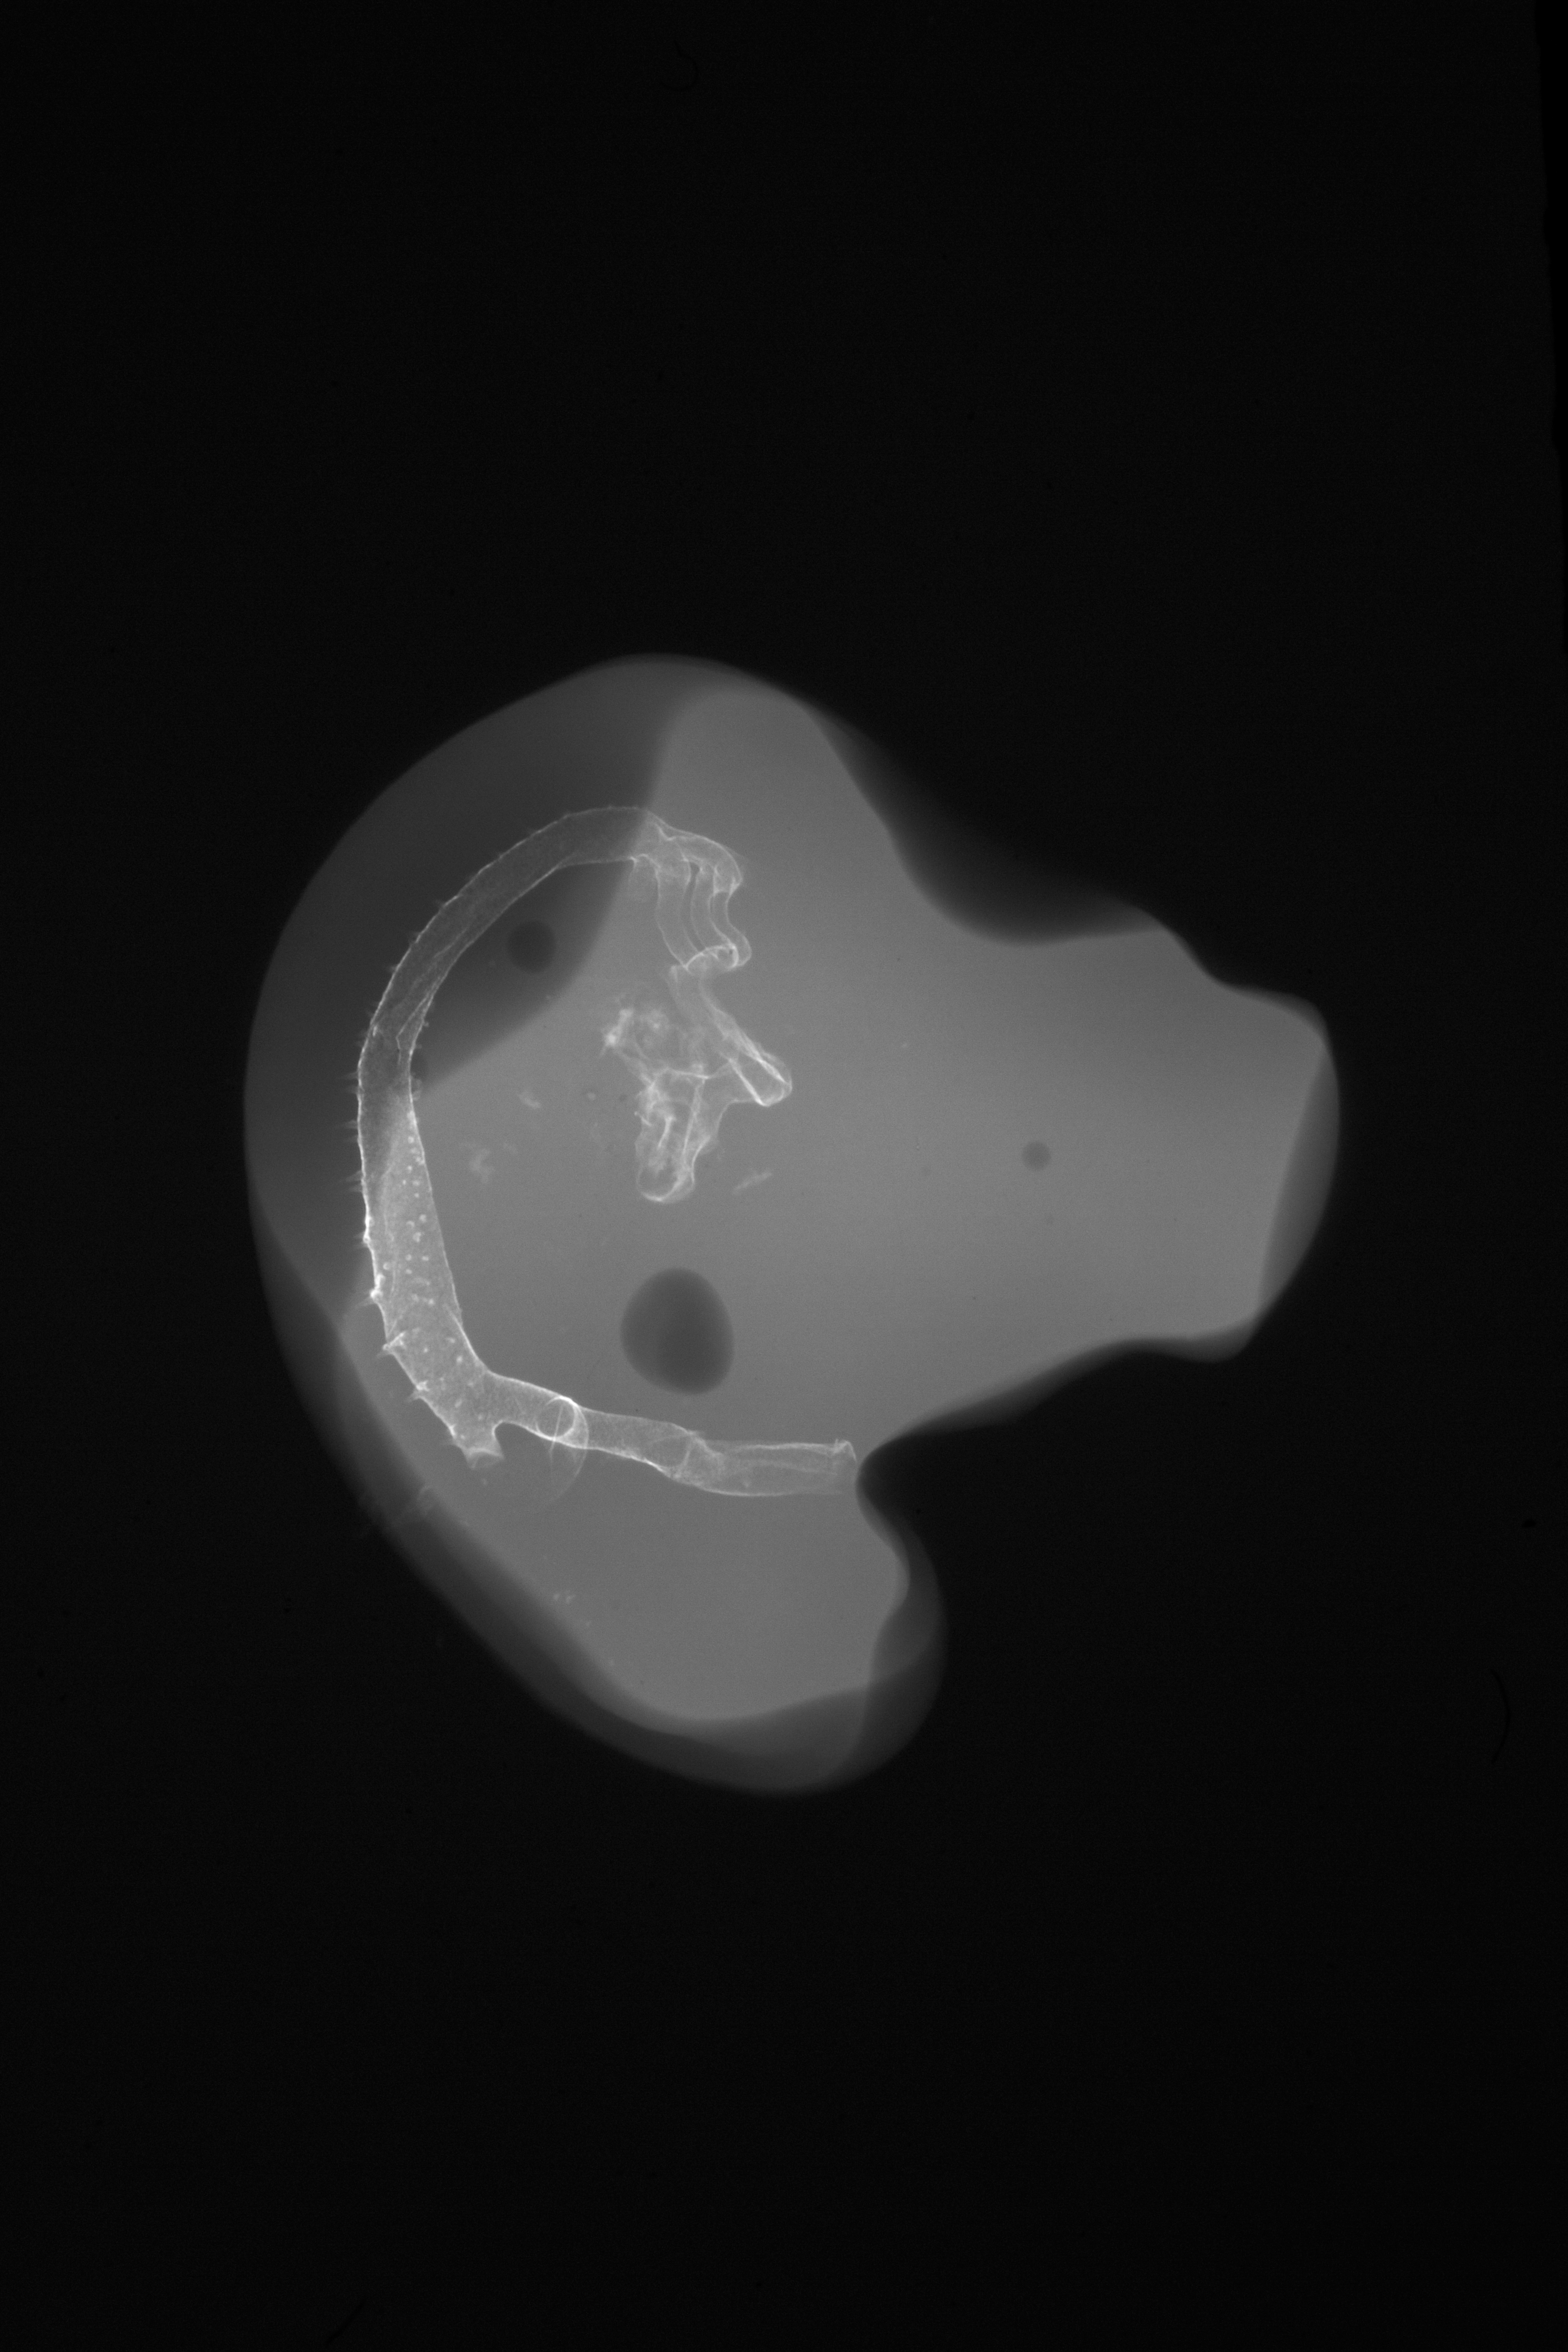

Chick Embryo Microangiography

Hamburger-Hamilton (HH) Stage 23 (approx. 4 days)

X-Ray Micrographs